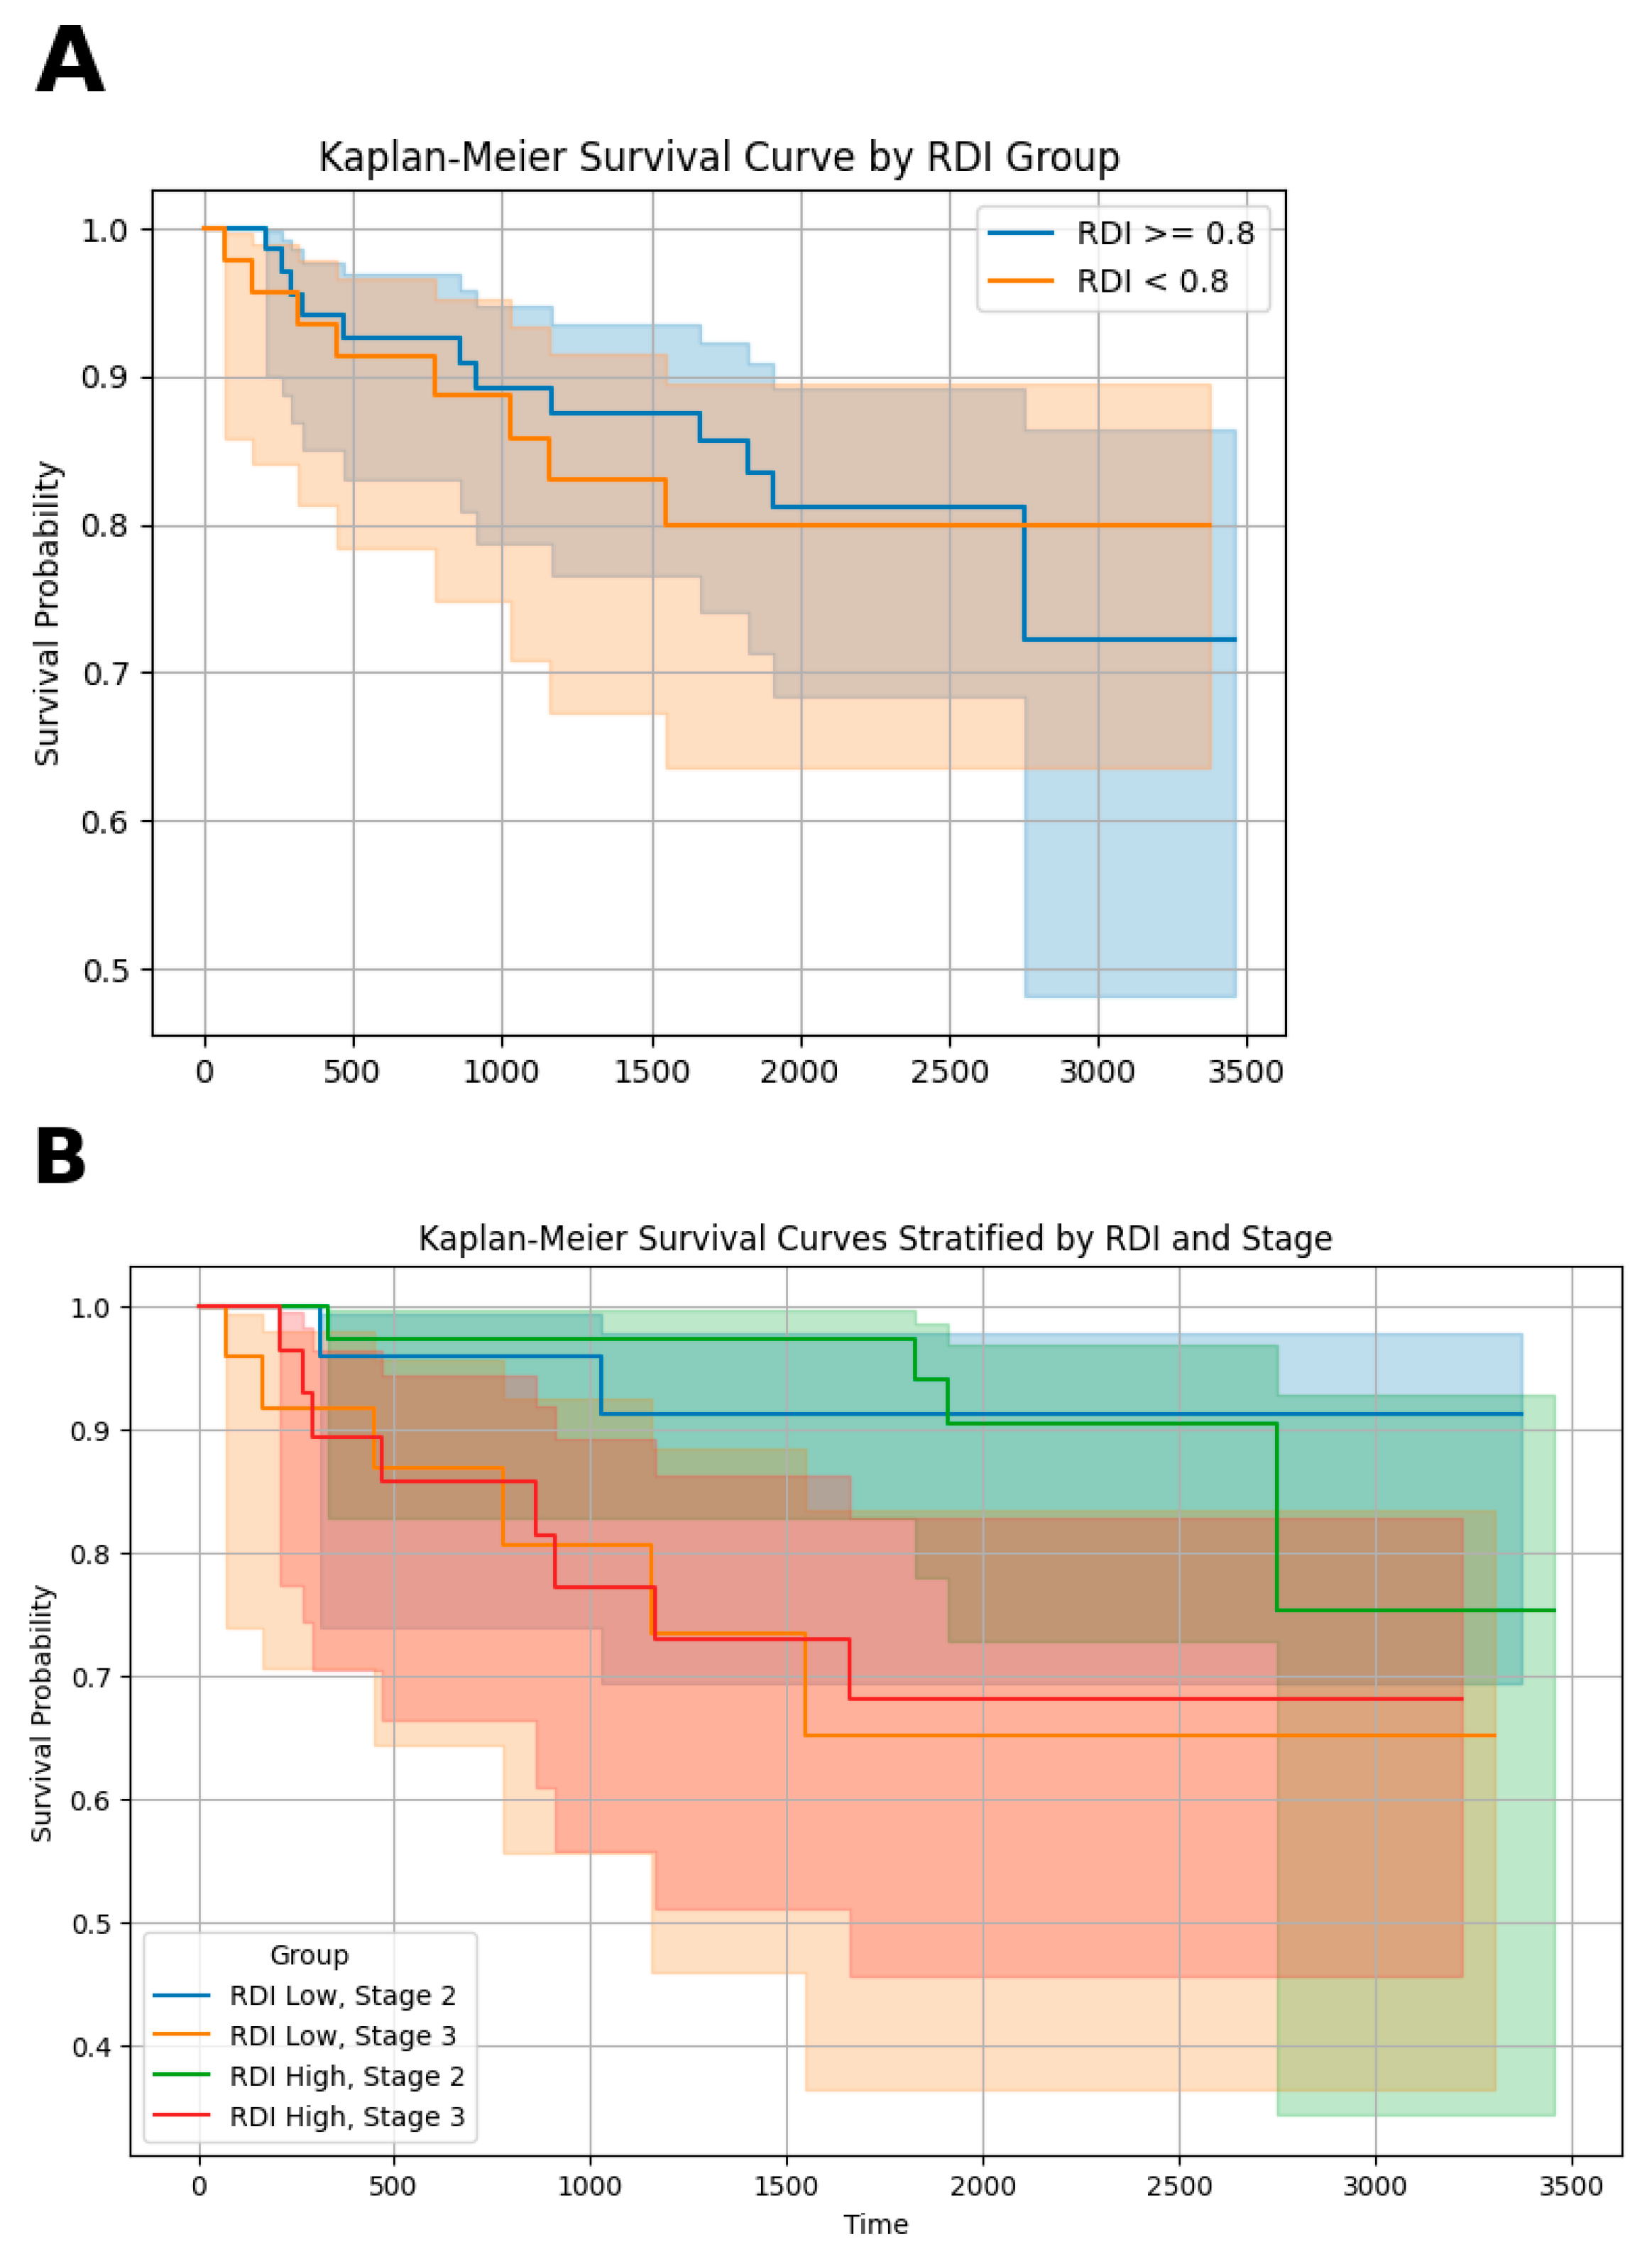

| AJCC Stage | ||||

| II | 34 (64.15%) | 24 (55.81%) | 8 (36.37%) | 64 (55.17%) |

| III | 19 (35.85%) | 19 (44.19%) | 14 (63.63%) | 52 (44.83%) |

| GLIM criteria | |||||

| No malnutrition | 51 (43.97%) | 0.844 ± 0.173 | |||

| Moderate malnutrition | 43 (37.07%) | 0.771 ± 0.208 | |||

| Severe malnutrition | 22 (18.97%) | 0.702 ± 0.232 | |||